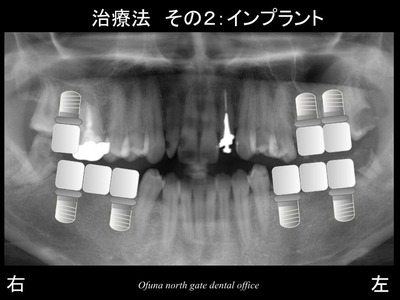

次にインプラント治療です。

固定式であるインプラント治療を希望されました。

しかし、こうしたインプラント治療には高額な治療費がかかってしまいます。

例えば、1歯欠損につき、必ず1本のインプラントを埋入するという治療計画を立てる歯科医師がいます。

こうした歯科医師が治療する場合には、9歯欠損になりますから

9本のインプラントが必要になります。

最終的な治療は以下になりました。

下顎は、左右とも2本のインプラントで3歯分を作製するブリッジ、

上顎は、左右ともに天然歯によるブリッジです。

このブリッジはもちろん保険で行います。